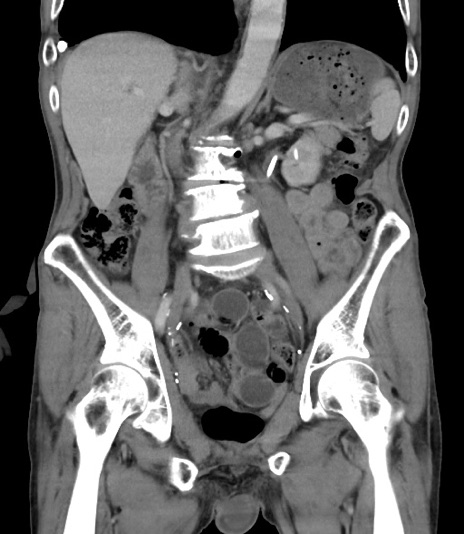

症例3(冠状断像)

【既往歴】膀胱癌にて膀胱全摘、両側尿管皮膚瘻